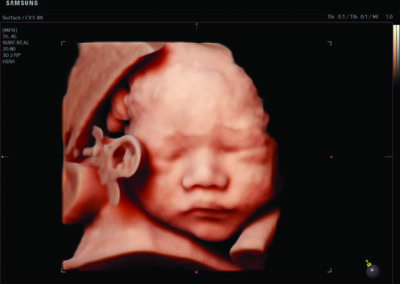

Comprehensive, advanced and expert MFM care for high-risk pregnancies